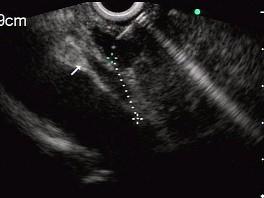

问题 男性,50岁,上腹隐痛,食欲不振3个月。1个月来出现黄疸且进行性加深,体重明显减轻,查体全身明显黄染,肝未触及,深吸气时可触到肿大胆囊底部,无触痛。化验血胆红素15mg/dl,尿检胆红素阳性图中胰腺病变可能的诊断是 ( )

选项 A.正常 B.胰腺囊肿 C.慢性胰腺炎 D.胰腺囊腺癌 E.胰腺癌

答案 E